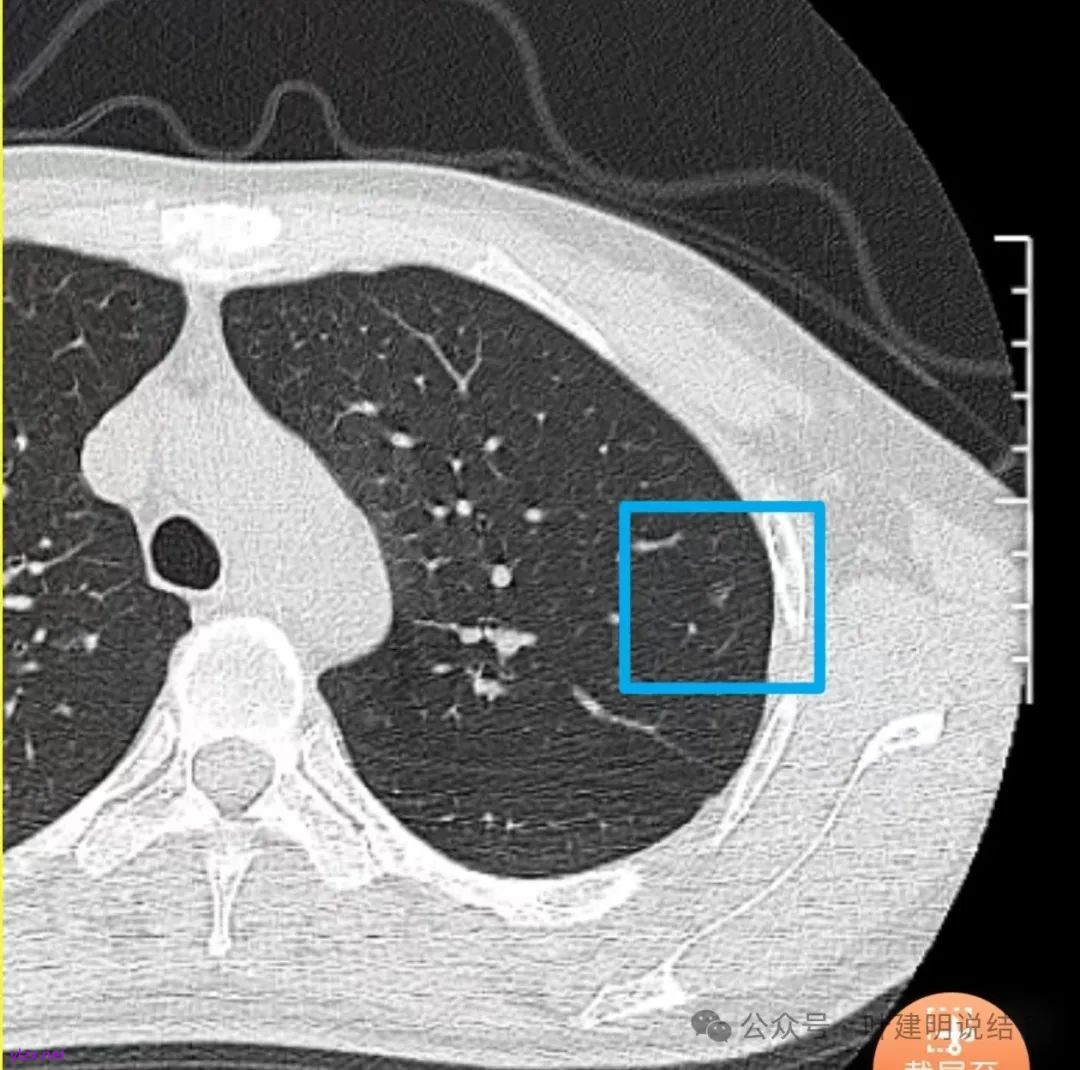

先来看2024年12月的影像:

右下叶磨玻璃结节伴空泡征,轮廓较清,瘤肺边界清楚。

表面不平,轮廓较清,有血管进入,边缘略显毛糙。

病灶内有少许偏实性成分,与血管关系较为密切,局部似有浅分叶的样子。

两肺多发结节,左侧黄色标注的考虑是肺泡上皮增生可能性大;蓝色的考虑肺泡上皮增生或者少许慢性炎可能性大;右侧红色宽起来并带有红色箭头的这处是主病灶,偏混合密度,整体轮廓较为清楚,边缘显得毛糙,从2024年12月份的来看,要考虑是肿瘤范畴,原位癌或者微浸润性腺癌可能性较大,也不能完全排除不典型增生。但是在2022年的时候,这个病灶的边上也有一个实性的微小结节,如果只看2022年的,这么小的实性结节,又比较圆,表面也显得较为光滑,是要考虑良性的,当然太小了需要动态观察。回头再重新来看2024年底的,发现绿色箭头所指的这个微小实性的较2022年几乎没有变,去仔细寻找2022年的,发现当时在实性结节旁边也有密度很淡的一点磨玻璃影(也可能真的就是一处,只是扫描不够薄,密度的变化有些突兀而已),而到了2024年12月份,实性微小这处没有明显变化,但是原来很淡的磨玻璃变成了混合磨玻璃,范围也明显扩大。所以总体来看右肺下叶这处是考虑恶性的,而且从磨玻璃结节角度来讲,还是生长比较快的,就是说还是有一定风险的。加上左侧还有两处也是磨玻璃持续存在,虽然边缘轮廓显模糊一点,但多年以后也可能仍然要变成原位癌或者微浸润性腺癌之类的东西。通盘考虑以后,我倾向于右侧近期单孔胸腔镜下微创局部切除,左侧随访观察,等到有进展并风险增加再来考虑处理。意见供参考!